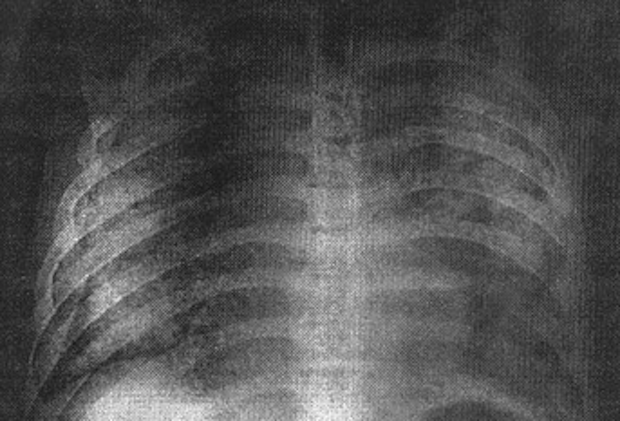

後期症状には呼吸困難が伴い、直ちに医療処置が必要となり、死亡率は 30%だ。

感染すると患者の 3人に1人が死亡し、承認された治療法やワクチンはない。